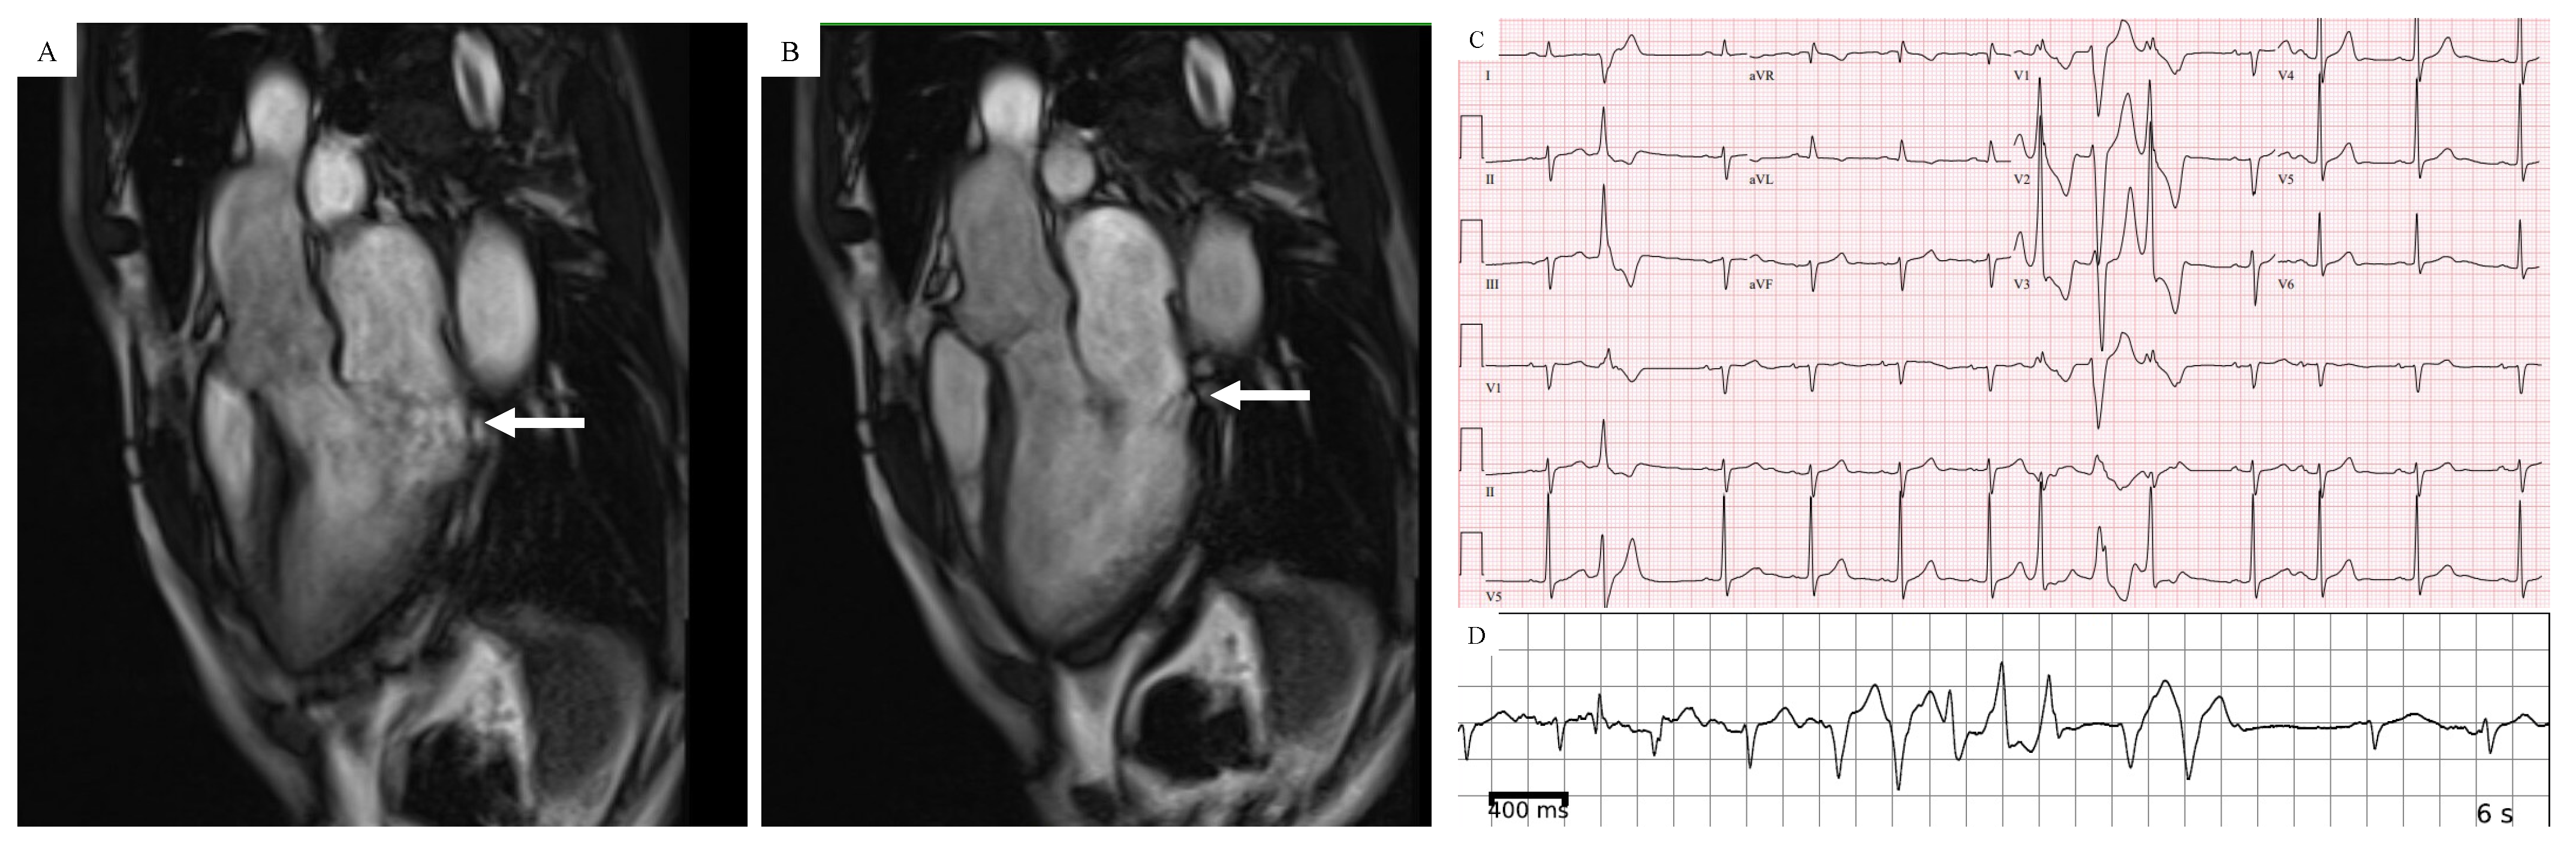

Figure 4.

Patient with AMVP who has evidence of mitral annular disjunction (MAD) by CMR in a 3-chamber long-axis view in systolic frame (A) and diastolic frame (B). (C) 12-lead ECG showing PVCs with alternating axes. (D) Complex ventricular ectopy captured on ambulatory ECG monitoring.

Cardiac magnetic resonance (CMR) has gained popularity as a noninvasive imaging modality for the detection of high-risk features in MVP patients that can be used in risk stratification [10,72]. These features include MAD, systolic curling and fibrosis (myocardial and/or papillary scar) manifested as late gadolinium enhancement (LGE). Figure 4A,B show an example of a patient with AMVP who had evidence of MAD on CMR. Fibrosis is most often detected in the papillary muscles (predominantly the posteromedial) or inferobasal region of the LV under the posterior mitral valve leaflet [6]. Constant Dit Beaufils et al. observed replacement myocardial fibrosis in 110 of 400 (28%) MVP patients who underwent CMR (91 with myocardial wall including 71 with basal inferolateral wall; 29 with papillary muscle) [73]. Additional fibrosis patterns include subendocardial fibrosis and diffuse interstitial fibrosis (T1 mapping/ECV). Given the association of myocardial fibrosis with SCD, the detection of endocardial fibrosis is an essential step to stratify high-risk SCD patients. A study with 41 participants showed reduced post-contrast times in patients with MVP, suggesting diffuse LV myocardial fibrosis. Kitkungvan et al. studied 356 patients who underwent CMR, dividing them into MVP and non-MVP patients, and he found a significantly higher prevalence of LV fibrosis in the MVP patients group [74]. However, another recent study failed to find any significant associations between complex VA in MVP patients and T1/ECV values [75]. Scatteia et al. evaluated the cardiac MRI of 47 consecutive patients with MVP compared with a group of patients without MVP and noted significantly lower signal intensity in papillary muscles in the MVP group [51]..